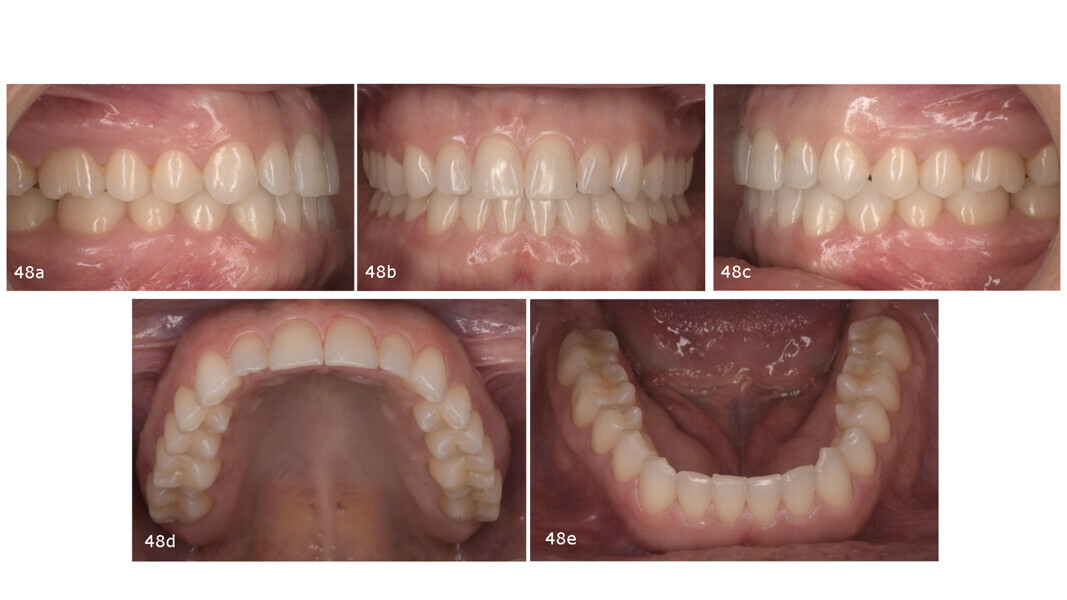

Extra-orally, two aspects are worth highlighting: the significant improvement in the smile, in that the patient no longer showed posterior gingiva, owing to intrusion of the maxillary posterior teeth; and the slimmer facial appearance, thanks to muscle relaxation and reduction in the size of the masseter muscles (Fig. 47). Intra-orally, Class I molar and canine relationships had been achieved, and the anterior open bite had been closed, resulting in proper overjet and overbite. The positive torque applied to the maxillary and mandibular posterior segments had improved the arch form. The maxillary incisors were proclined (U1–PP from 105° pretreatment to 112° post-treatment) and the mandibular incisors retroclined (IMPA from 98° pretreatment to 93° post-treatment; Fig. 48).